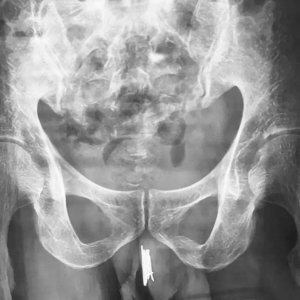

本报讯(华商晨报记者 王丽娜)一年多时间频繁尿血,沈阳35岁的男子求医无果后,到沈阳军区总医院泌尿男科就诊。 经过详细检查后,医生发现,男子的尿道内竟然有多达15根家用缝衣针。这些钢针都是男子自己在一年左右的时间内陆续放进去的。 医生提醒,尿道口异物患者并不少见,油笔芯、温度计、铁丝在临床上都看到过,但是这样做是非常危险的,严重了可能无法排尿,需要手术改道甚至终身残疾。 罕见病例: 男子尿道口内插15根缝衣针 6月20日15时许,沈阳军区总医院泌尿男科副主任医师曹志强开始了一台艰难的手术。 台上的患者是一名35岁的未婚男子,尿道内塞入了15根长短不一的缝衣针,最长的约8~10厘米,最短的也有5~6厘米长。 男子在家属的陪同下,最近因尿道疼痛不适多家医院就诊后,转到沈阳军区总医院院。拍片提示,针均卡在大概膜部尿道位置。 医生了解到,从一年多前开始,男子分多次由尿道外口塞入了钢针,均为针鼻儿一头向内、针尖向外,因此塞入时并没有很疼。 但钢针留在体内无法自行取出,时间长了,尿痛、尿血等问题让他难以忍受,只得多方求医。 如此多的尿道异物,传统的治法肯定是开刀取出,但患者却不希望开刀,因此跑了多家医院也没有治好。 为此,曹志强医生在泌尿男科主任刘龙的指导下,选择了电切镜、输尿管镜、腹腔镜多种器械的手术方案,通过几根导丝将器械从尿道口送入尿道,将钢针一点点“拔”了出来。 医生提醒: 癖好不是病但需注意安全 “手术大概做了一个半小时左右,结束的时候我的手都累得发抖了,满头是汗,确实不容易。”曹志强说,其实这样的患者,在男科并不算罕见。 曹志强表示,男科还曾接诊过尿道内塞油笔芯、温度计、铁丝等异物的患者,男女都有。“有学者称这种有特殊癖好的人为‘性怪癖’的一种,尿道疼痛刺激或摩擦刺激能够使他们获得一种满足感。” 医生表示,这并不能说是一种疾病,但在方法上确实需要注意安全至上。因为钢针、笔芯、温度计等异物一方面不够清洁,另一方面容易折断或者存在易伤人的尖锐端,极易对人体造成损伤。一旦异物卡在体内无法取出,还会造成尿道狭窄、尿漏等问题,最严重的将无法排尿。 钢针卡在尿道外口 |